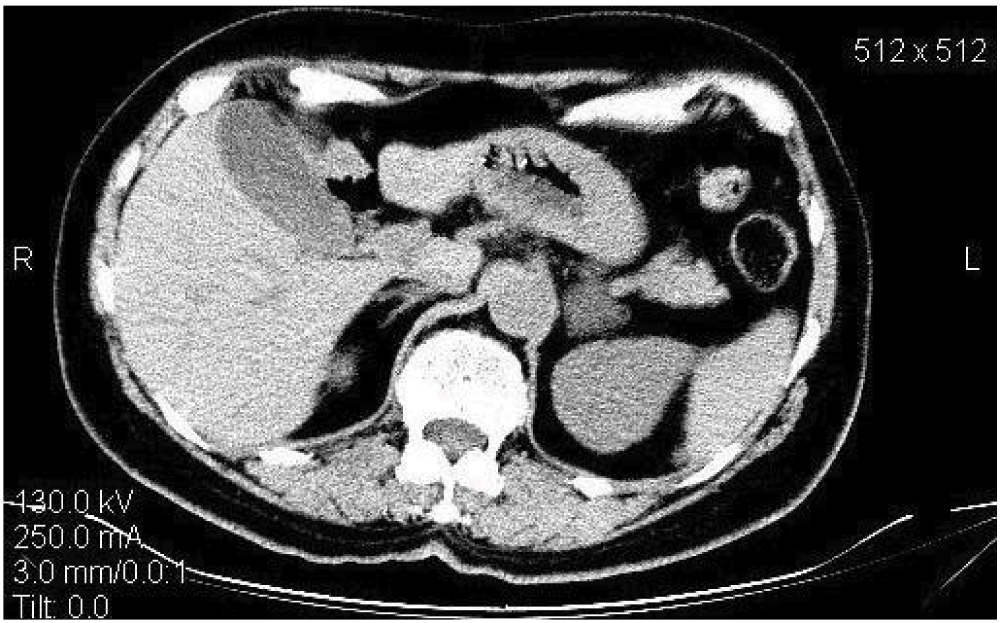

The association of resistant hypertension and hypokalemia raised the suspicion of PA. Baseline laboratory data are shown in Table 1. Treatment with ACE-inhibitors and diuretics was stopped for 20 days to investigate her Renin-Angiotensin-Aldosterone-System (RAAS) before the next presentation to our clinic. In our unit the aldosterone to renin ratio (ARR) is used as a screening test for PA. In patients with elevated basal ARR (>750 pmol/l per ng/ml/h) a confirmatory test (Captopril challenge test) is performed. The diagnosis of PA is confirmed if the aldosterone is >330 pmol/l at the 90th minute after the oral administration of 50 mg of Captopril, with the patient asked to remain in a sitting position throughout the test. In our patient the basal and post-captopril aldosterone to renin ratio was 1260 and 3545, respectively. Suppressed plasma rennin activity (PRA) was measured at the beginning and the end of the test (<0.2 ng/ml, normal range 0.3–3). Basal aldosterone was 252 pmol/l and 709 pmol/l at the end of the test. The adrenal CT scan showed a 35 mm nodule in the left adrenal gland (Figure 1) and aldosterone-producing adenoma (Conn’s adenoma) was diagnosed. The patient was operated on in August 2008. A tumor of 35 mm was found and histology (hematoxylin and eosin) data showed a tumor of adrenal cortex origin, consisting of light cells.

Figure 1. CT scan visualizing 35 mm tumor in the left adrenal gland and a normal right adrenal gland.